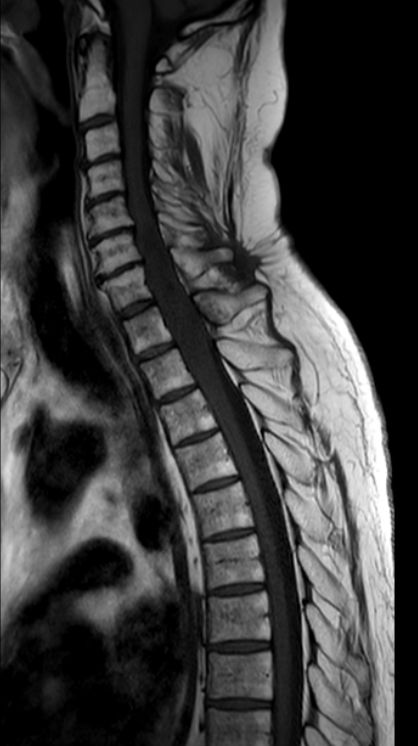

Myelon 63-jähriger Mann mit Querschnittssymptomatik. Auch nach Dekompression keine Motorik oder Sensorik der unteren Körperhälfte.

MRT T1W-Bild

MRT T2W-Bild

MRT T2W-Bild. Hier ist die Degeneration des Myelons unterhalb des Tumors erkennbar.